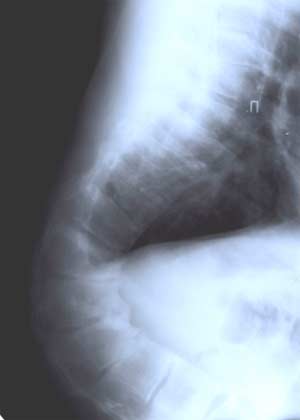

Рентгенологический признак завершенности прогрессирования сколиоза.

Окончание оссификации апофизов гребней подвздошных костей в возрасте 16-18 лет. Задержка оссификации апофизов тел позвонков наблюдается как при идиопатическом (диспластическом) так и при паралитическом сколиозе на вогнутой стороне. На выпуклой стороне искривления характерно образование реберного горба (чем больше искривление тем больше острый угол реберного горба).

Рентгенологический признак прогрессирования сколиоза.

Начало периода оссификации кольцевых апофизов тел позвонков, т. е. с началом периода интенсивного роста скелета. Это, как правило, с 8 до 15-16 лет.

Приведенные выше признаки прогрессирования сколиоза имеют существенное значение в диагностике этого заболевания и в выявлении наиболее неблагоприятно претекающих его форм. Раннее выявление таких форм позволяет своевременно прибегнуть к оперативному вмешательству.